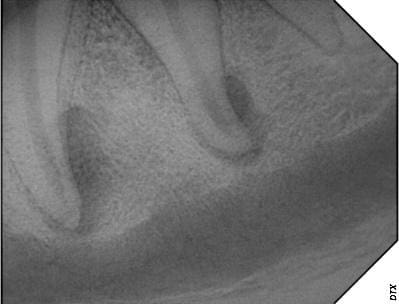

Figure 5. (A) A molar a cavity that can be treated with a restorative filling and (B) a tooth with an end-stage cavity that requires extraction.

(A)

(B)